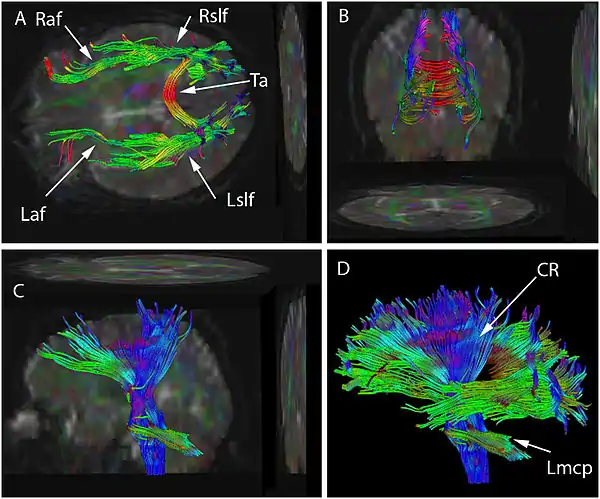

On voit ici les vues supérieures (A), postérieures (B) et latérales (C et D).

La tractographie est réalisée grâce à l'imagerie du tenseur de diffusion. L'IRM de diffusion, introduite, notamment pour son potentiel en neuroimagerie par Denis Le Bihan dès 1985 [1],[2] permet d'obtenir des images de la diffusion moléculaire, notamment de l'eau. Une évolution de l'IRM de diffusion, l'imagerie du Tenseur de Diffusion [3],[4], permet de caractériser la diffusion moléculaire dans les 3 dimensions de l'espace. La diffusion libre se produit de manière homogène dans toutes les directions (mouvement brownien). On l'appelle diffusion isotropique. Si l'eau diffuse dans un milieu avec des barrières, la diffusion sera privilégiée dans certaines directions. On l'appelle diffusion anisotropique. Dans un tel cas, la mobilité des molécules à partir de leur origine de départ a une forme différente d'une sphère. La forme peut-être ellipsoïde. Cette technique est appelée technique d'imagerie du tenseur de diffusion. Les barrières peuvent être de multiples types : membranes cellulaires, axones, gaines de myéline, etc. Dans le cerveau, la principale barrière est la gaine de myéline. Des faisceaux d'axones forment une barrière empêchant une diffusion perpendiculaire et un chemin pour la diffusion parallèle le long de l'orientation des fibres. On s'attend à ce que la diffusion anisotropique soit augmentée dans les zones d'ordre axonal maximum. Dans certaines pathologies, la structure des axones est perturbée comme dans les traumatismes, les tumeurs ou les inflammations. L'anisotropie, par destruction ou désorganisation des barrières est donc augmentée. L'anisotropie est mesurée de différentes manières. L'une d'entre elles consiste à évaluer un ratio appelé anisotropie fractionnelle (AF). Une anisotropie de 0 correspond à une sphère parfaite alors qu'un ratio à 1 correspond à une diffusion linéaire idéale. Des trajets bien délimitables ont une AF plus grande que 0,20. Peu de régions ont une AF de plus de 0,80. La valeur donne une information sur la non-sphéricité de la diffusion mais ne donne pas d'information sur sa direction. Chaque anisotropie est liée à une orientation sur un axe prédominant (direction prédominate de la diffusion) Des programmes informatiques sont capables d'extraire cette information directionnelle. Cette information additionnelle est difficile à représenter sur des images en 2D en échelles de gris. Pour surmonter ce problème, un code coloré est ajouté. Des couleurs basiques informent sur l'orientation des fibres dans un système avec des coordonnées dans les 3 dimensions. On parle de plan anisotropique. Conventions de couleurs :

- Le rouge indique une direction sur l'axe de X: droite à gauche ou gauche à droite.

- Le vert indique des directions selon l'axe des Y : postérieur vers antérieur ou antérieur vers postérieur.

- Le bleu indique des directions sur l'axe des Z : des pieds à la tête ou de la tête aux pieds.

Il faut noter que la technique est incapable de discriminer les directions positives ou négatives (dans un sens ou dans l'autre) d'un même axe.